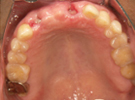

50代女性

![]() |

治療前 |

||

治療中。仮歯。 左上の奥にインプラント埋入。 噛みあわせ治療を行いました |

治療後 全体の歯で食事がおいしくできるようになったと喜んでおられました。 |